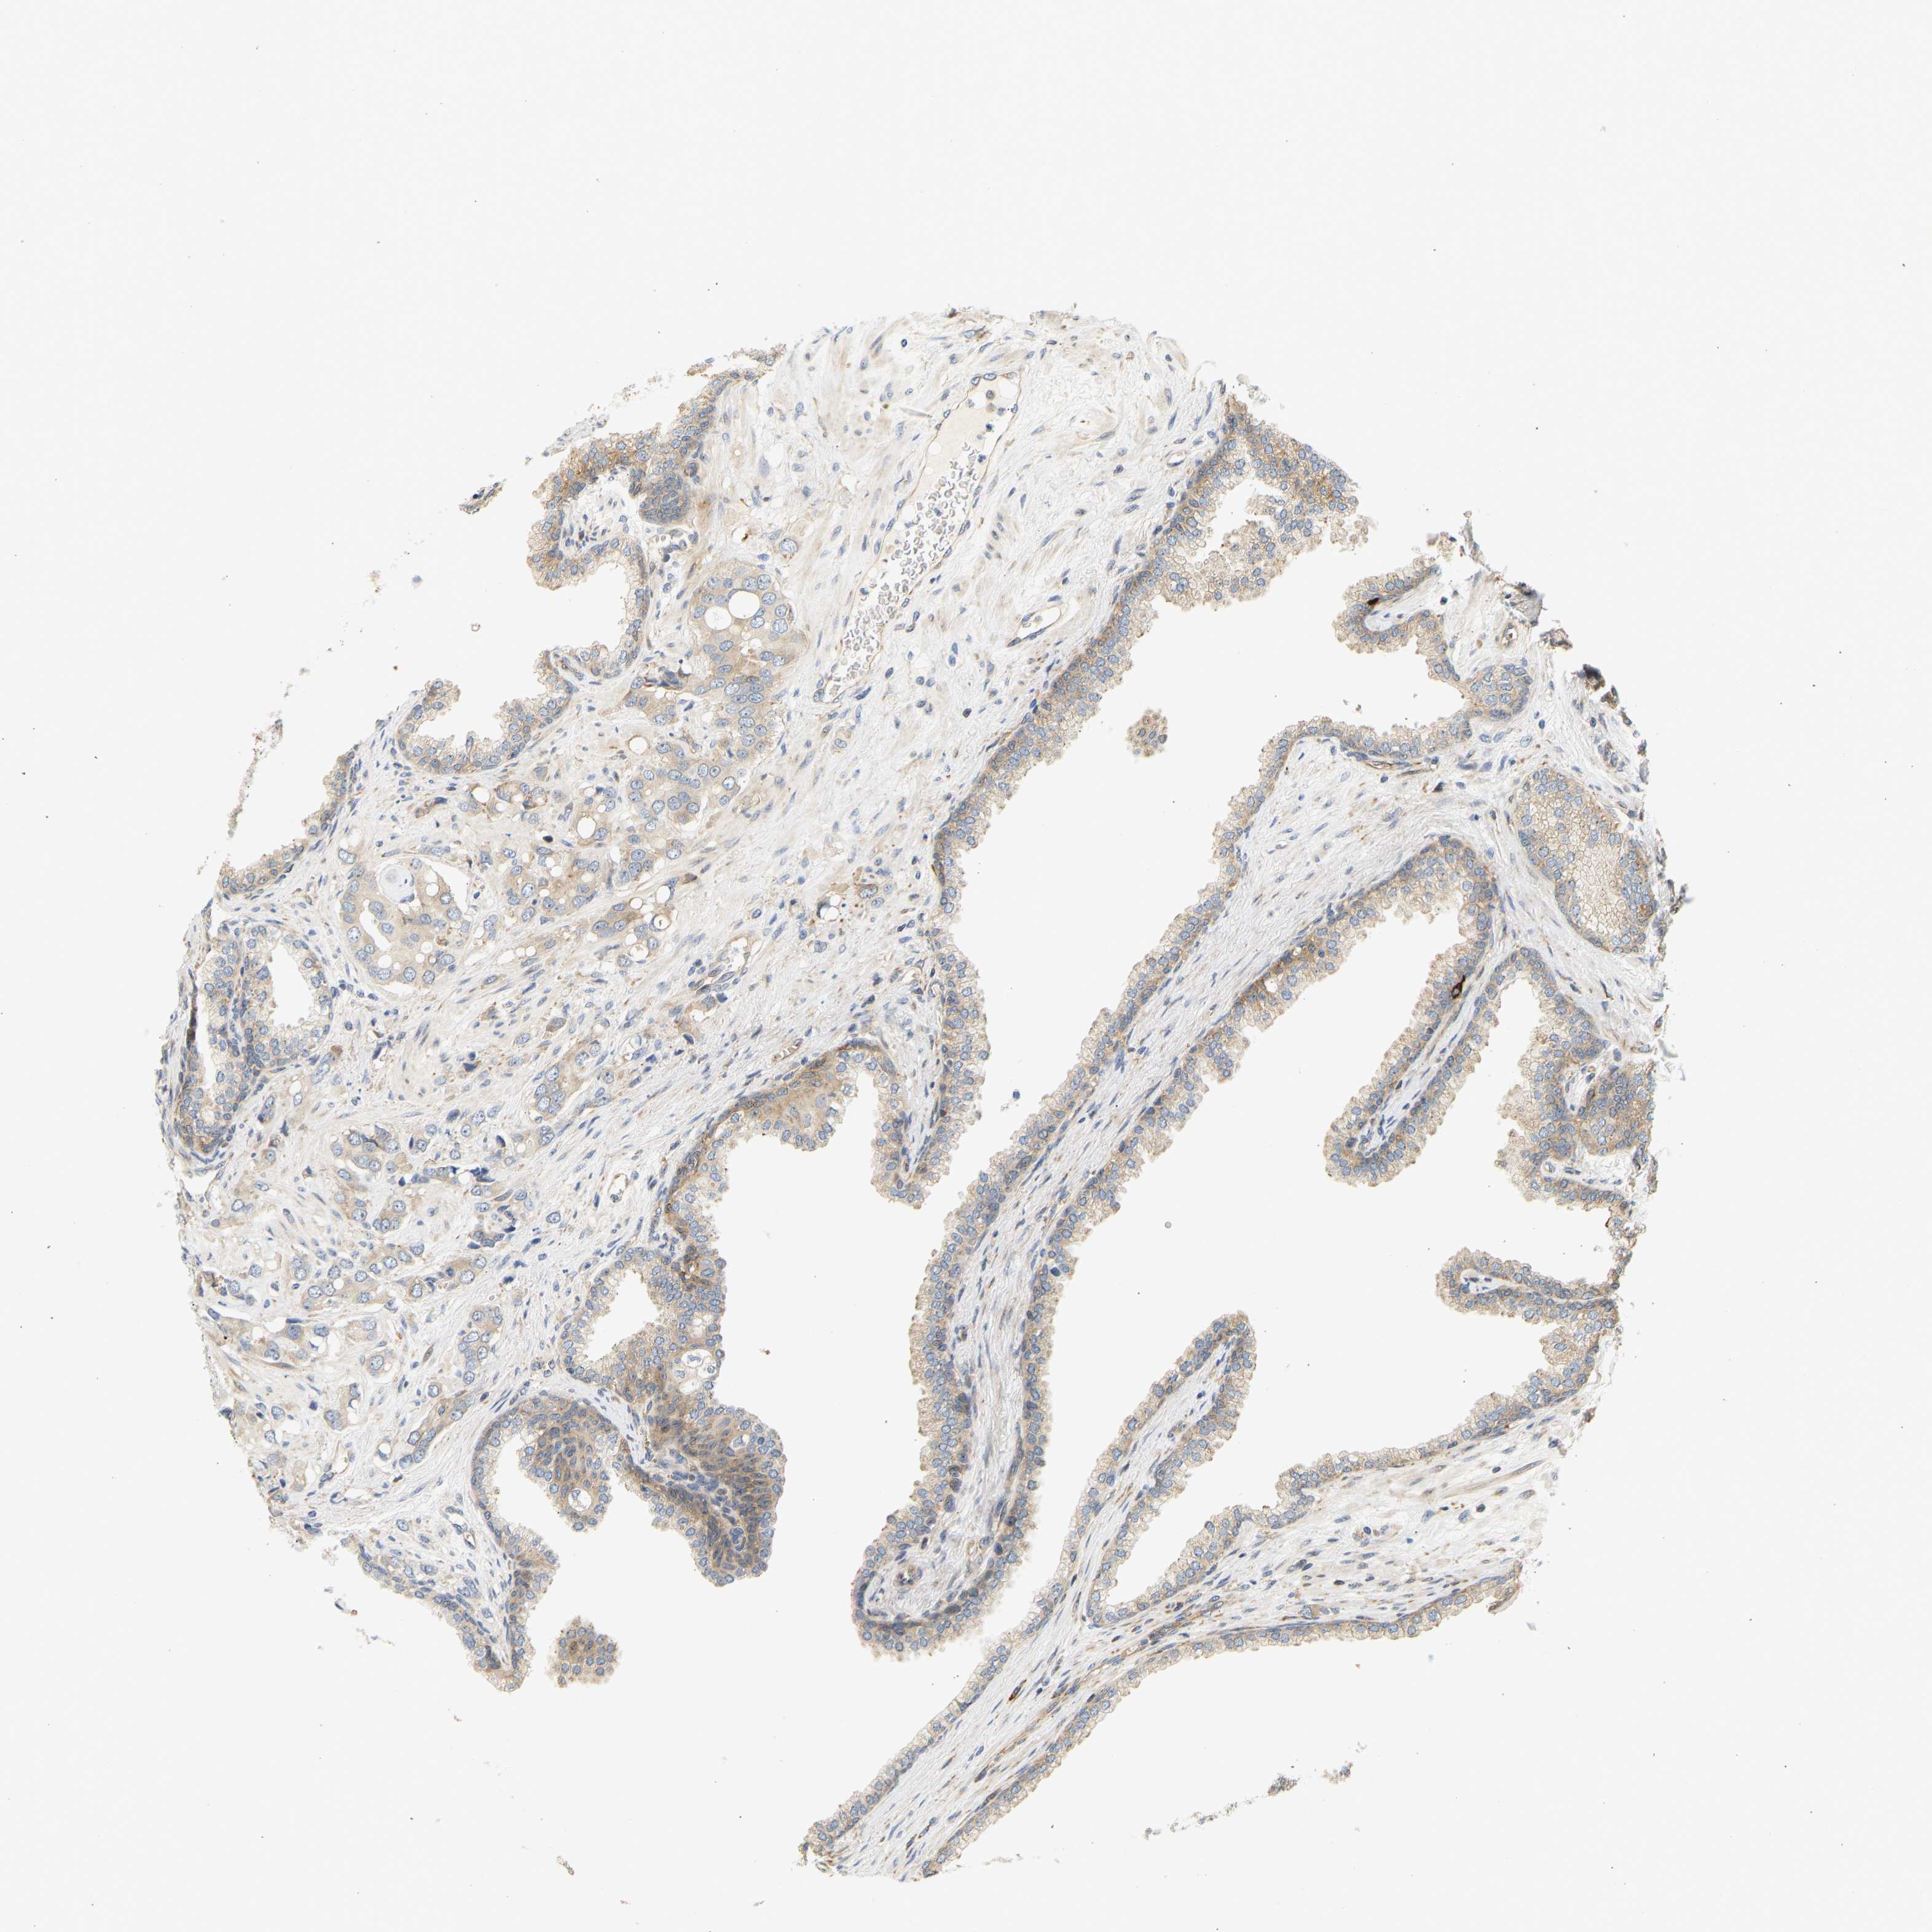

PROSTATE CANCER - Protein expressioni

A mouse-over function shows sample information and annotation data. Click on an image to view it in a full screen mode. Samples can be filtered based on level of antibody staining by selecting one or several of the following categories: high, medium, low and not detected. The assay and annotation is described here.

Note that samples used for immunohistochemistry by the Human Protein Atlas do not correspond to samples in the TCGA dataset.

Antibody stainingi

Antibody staining in the annotated cell types in the current human tissue is reported as not detected, low, medium, or high, based on conventional immunohistochemistry profiling in selected tissues. This score is based on the combination of the staining intensity and fraction of stained cells.

Each image is clickable and will lead to virtual microscopy that enables deeper exploration of all samples and also displays staining intensity scores, fraction scores and subcellular localization as well as patient and tissue information for each sample.

Antibody HPA018504

Staining

High

Medium

Low

Not detected

Intensity

Strong

Moderate

Weak

Negative

Quantity

>75%

75%-25%

<25%

None

Location

Nuclear

Cytoplasmic/membranous

Cytoplasmic/membranous,nuclear

Adenocarcinoma, High grade

Adenocarcinoma, Low grade